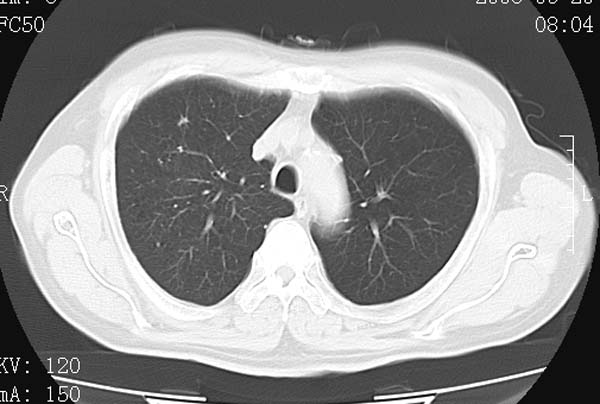

以下是引用守望可可西里在2008-6-24 1:11:00的发言:[br][br] 考虑为周围型肺癌:[br] 1.分叶结节,形态极不规则,蟹足样伸展的恶性浸润特征比较明确。[br] 2.磨玻璃影中由多个更高密度小结节聚集呈梅花瓣样。[br] 3.局部胸膜凹陷征比较明确。[br][br] 另:纵隔胸膜明显增厚、粘连。

以下是引用zjzjr在2008-6-24 11:19:00的发言:[br]支持左下肺周围型肺癌伴右肺转移,纵隔淋巴结转移,心包积液.

以下是引用zhangling在2008-6-24 14:56:00的发言:[br]我们科室意见报告为[br][br]1考虑左下肺周围型肺癌[br]2右肺小结节考虑转移瘤,纵隔淋巴结转移[br]3心包积液. [br] 各位老师分析的相当好 谢意[br]